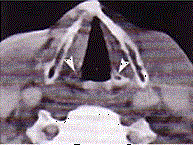

问题 男,60岁,因吞咽疼痛伴咽异物感一个月就诊。间接喉镜下检查发现会厌侧面轻度糜烂、不光滑、隆起,既往有吸烟史。 CT检查见下图,进一步的检查是 ( )

选项 A、放疗 B、活检送病理 C、密切观察 D、抗生素治疗 E、纤维喉镜检查以明确病变范围

答案 B